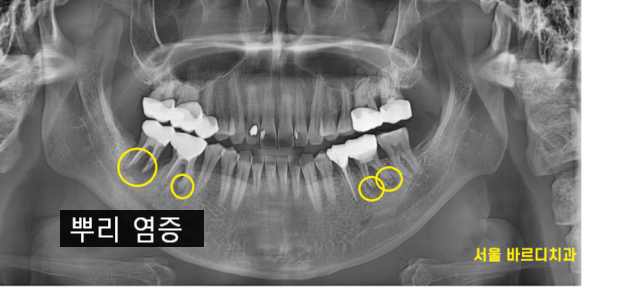

231204

강일동 치과에서 검사한 사진입니다.

원인을 발견하기 위해 시행한 검사에서

뿌리 끝 염증이 잡혀있는 치아가 많았습니다.

이전에 신경 치료하셨던 부위로

염증이 진행된지 오래된 것으로 보였습니다.

잇몸뼈 녹음도 관찰 됐거든요~